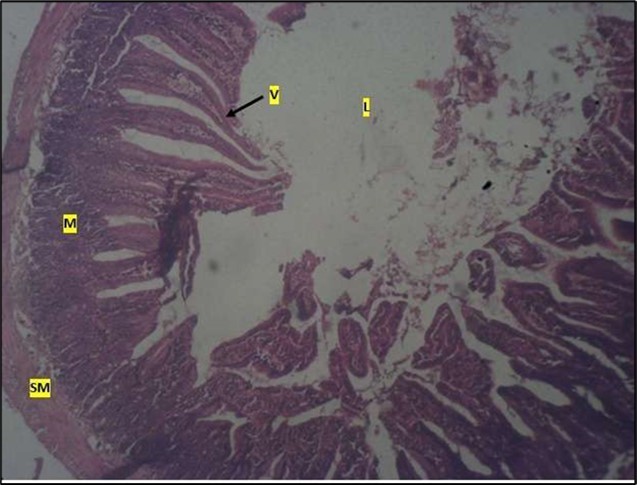

Histological examination of the small intestine result in control animals revealed a normal architecture with the red pulp and white pulp with no pathological observation Figure 2. Administration of Abelmoschus esculentus at low dose shows an increased cellularity with numerous cells in the Mucosa and the villi projecting towards the lumen. Focal metaplasia of mucosal cells alongside villous disruption was also observed (Figure 3). The high dose group showed normal cellular architecture with no villous disruption (Figure 4).

Figure 2.Control showing the mucosa with intestinal villi (v) projecting towards the lumen (l) and the underlying smooth muscle layer (sm) all appearing normal